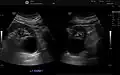

The complex cyst can be further evaluated with doppler ultrasonography, and for Bosniak classification and follow-up of complex cysts, either contrast-enhanced ultrasound (CEUS) or contrast CT is used.[13]

-

Renal cyst as seen on abdominal ultrasound -